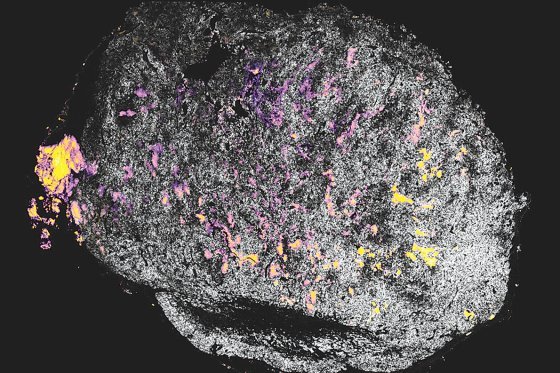

MIT 연구진이 사이토카인(IL-12·분홍색)에 수산화알루미늄(노란색)을 결합한 단백질을 종양에 전달한 뒤 종양의 모습이다.

IL-12가 종양 주변의 면역세포를 활성화시키면 면역세포(T세포)가 암세포를 공격하면서 치료가 이뤄진다. MIT 제공

MIT 연구진이 사이토카인(IL-12·분홍색)에 수산화알루미늄(노란색)을 결합한 단백질을 종양에 전달한 뒤 종양의 모습이다.

IL-12가 종양 주변의 면역세포를 활성화시키면 면역세포(T세포)가 암세포를 공격하면서 치료가 이뤄진다. MIT 제공

MIT 연구진이 사이토카인(IL-12·분홍색)에 수산화알루미늄(노란색)을 결합한 단백질을 종양에 전달한 뒤 종양의 모습이다.

IL-12가 종양 주변의 면역세포를 활성화시키면 면역세포(T세포)가 암세포를 공격하면서 치료가 이뤄진다. MIT 제공

MIT 연구진이 사이토카인(IL-12·분홍색)에 수산화알루미늄(노란색)을 결합한 단백질을 종양에 전달한 뒤 종양의 모습이다.

IL-12가 종양 주변의 면역세포를 활성화시키면 면역세포(T세포)가 암세포를 공격하면서 치료가 이뤄진다. MIT 제공사이토카인은 신체의 면역체계를 제어하고 자극하는 신호물질로 사용되는 당단백질이다. 면역세포인 대식세포와 백혈구의 일종인 T림프구 등에서 분비돼 암세포를 공격하는 T세포를 활성화하는 역할을 한다. 인터류킨과 인터페론이 대표적인 사이토카인 단백질이다.